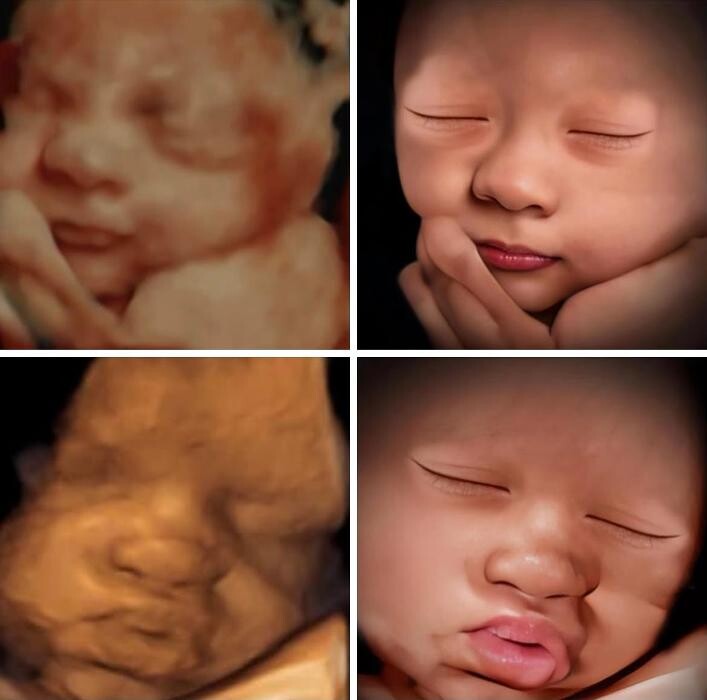

Discover an exceptional ultrasound experience at Miracle in the Womb, the premier pregnancy 3D/4D ultrasound and 8K Enhanced Imaging studio in Broken Arrow, Oklahoma. With their advanced technology and skilled technicians, they offer an unforgettable journey into the miracle of life. Experience the wonder of 3D ultrasounds, providing lifelike images that beautifully showcase your baby's features. Witness your little one in action with 4D ultrasounds, capturing real-time movements and creating cherished memories. Every tiny feature, from their adorable face to their dainty fingers and toes, is brought to life with astonishing precision. Conveniently located, Miracle in the Womb is the ideal choice for those searching for an ultrasound near them in Tulsa. Their welcoming studio and friendly staff create a comfortable environment for your visit. Trust their expertise and state-of-the-art technology to provide an exceptional ultrasound journey you'll cherish forever.